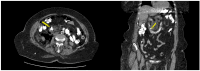

Background/Objectives: Perforations represent rare but serious complications in ERCP. Although several therapeutic algorithms have been proposed to properly address these potentially life-threatening events, there is still no clear consensus on their management. We conducted a single-center retrospective study in order to assess the incidence of ERCP-related perforations and their management, as well as clinical outcomes. Methods: The hospital's electronic database was searched in order to identify all the patients who developed ERCP-related perforations in the period 1 October 2018-30 June 2023. Perforations were classified according to the Stapfer classification. Conservative management included frequent abdominal examinations, the monitoring of vital signs, white blood cell count, complete bowel rest, nasogastric tube placement, and the administration of intravenous fluids and antibiotics. Endoscopic management included biliary stent placement and/or closing observed defects with clips. Results: We recorded eight (1.29%) cases of ERCP-related perforations out of the 619 procedures conducted. We observed six (75%) Stapfer type II and two (25%) type IV perforations. In all but one patient (87.5%), the indication for ERCP was bile duct stones. Seven patients (87.5%) were subjected to sphincterotomy (87.5%) and three (37.5%) to "pre-cuts". All but one patient was treated conservatively (87.5%), with two of them-in which type II perforations were recognized intraprocedurally-also receiving endoscopic treatment with stent placement. On the day of ERCP, one patient with a type II perforation was operated on; suturing of the duodenum followed by duodenal exclusion was applied. Management was successful in all the patients, with a mean hospitalization time of 16.6 ± 4.78 days. Conclusions: Conservative and endoscopic management appear to be associated with good outcomes in Stapfer type II perforations. Nevertheless, an individual multidisciplinary approach involving endoscopists and a hepatobiliary surgeon is essential in order to properly guide the treatment.

Figures